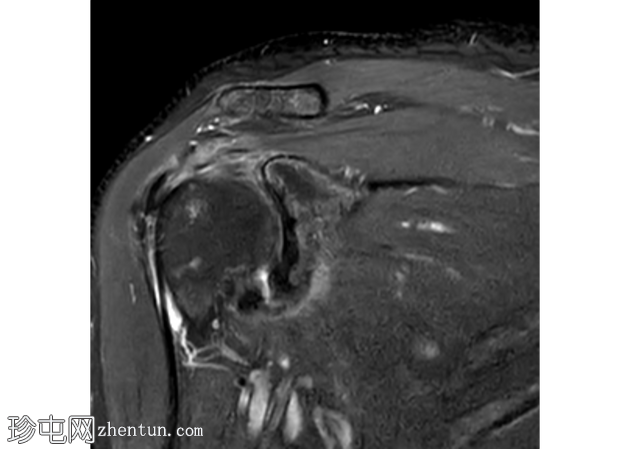

矢状面

T2

冈上肌腱滑囊侧存在部分厚度撕裂,肌腱物质内分层延伸约2厘米,与滑囊侧分层部分厚度撕裂相符。伴有间质性肩胛下肌腱(SST)撕裂。冈上肌体积轻度减少。

冈下肌腱、小圆肌腱和肩胛下肌腱完好,无明显撕裂迹象。

冠状面可见盂唇上方T2高信号,提示SLAP损伤。SLAP损伤延伸至肱二头肌长头,矢状面清晰可见。肱二头肌长头腱正常位于肱二头肌沟内,周围积液极少。

肩胛下肌隐窝和喙突下滑囊内有少量积液。

轻度肩锁关节病,特征为轻度肥大、少量关节内积液和微量肩峰下积液。

轻度盂肱关节积液。伴有肩关节囊增厚和水肿,提示反应性关节囊炎。

未发现骨髓水肿或骨折。